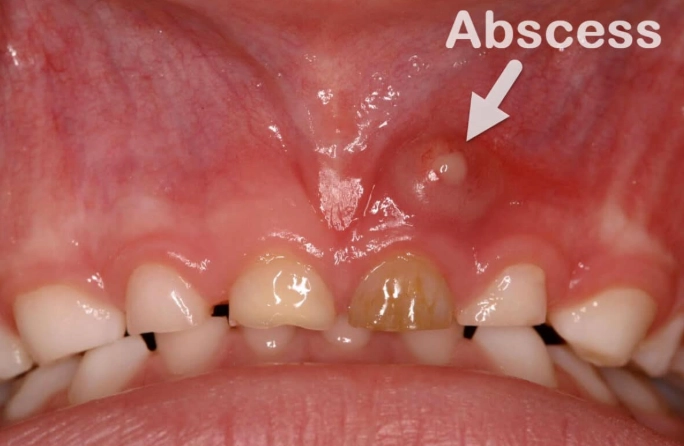

Then come the other guests to this unpleasant party. You might notice sudden sensitivity to hot and cold temperatures that lingers long after the source is gone. Your gums around the tooth may become red, swollen, and shiny. In some cases, the swelling can be significant, causing your face to look puffy on one side. You might even be able to see or feel a pimple-like bump on your gums near the root of the tooth – that's a draining fistula, and it's a classic sign of a tooth abscess trying to release pressure.

It's also helpful to know there are different types, which start in different places. A periapical abscess happens at the very tip of the tooth's root, usually from an untreated cavity or trauma that lets bacteria infect the pulp (the tooth's nerve center). A periodontal abscess starts in the supporting bone and gum tissues next to the tooth root, often from advanced gum disease. The treatment approach can differ slightly based on the type.

No. The infection might occasionally drain through the gum, which can temporarily relieve pain and pressure. This can fool you into thinking it's healing. But the source of the infection—the bacteria inside the tooth or deep in the gum pocket—is still there. It will almost certainly flare up again, often worse than before. Professional treatment is the only way to resolve it permanently.